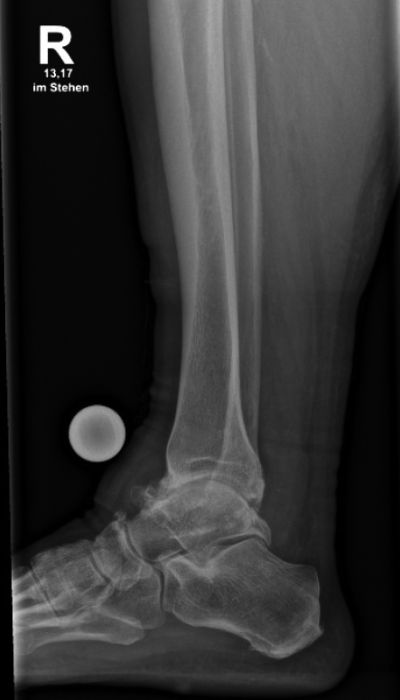

Eine ausführliche Anamnese und körperliche Untersuchung ist der Grundstein der Diagnostik und meistens bereits richtungsweisend. Typisch sind Schmerzen, Schwellung, Instabilität, Belastungseinschränkung sowie eine verminderte Beweglichkeit im oberen Sprunggelenk. In der klinischen Untersuchung sollte auf lokalen Druckschmerz, Bandinstabilitäten und Achsfehlstellungen geachtet und simultan die Funktion bzw. Beschwerden in den Nachbargelenken erfasst werden. Die Röntgen-Bildgebung sollte unter Belastung der betroffenen Extremität durchgeführt werden. Insbesondere der Mortise-view (Abbildung a) und die seitliche Aufnahme (Abbildung b) ermöglicht eine gute Beurteilung der Gelenksituation. Eine Ganzbeinaufnahme sollte erwogen werden, um statische Ursachen wie zum Beispiel kniegelenksnahe Achsdeformitäten zu detektieren. Bei Achsfehlstellungen, welche auf einer Rückfußproblematik basieren, ist der Hindfoot-View ein wichtiges diagnostisches Hilfsmittel. Bestehen ligamentäre Instabilitäten, eine unklare Situation der Nachbargelenke oder anzunehmende degenerative Sehnenveränderungen, kann eine MRT zur weiteren Therapieplanung sinnvoll sein (6). Bei komplexen knöchernen Situationen, insbesondere nach Frakturen mit eventuell vorhandenen Implantaten, kann die Computertomografie (CT) die Diagnostik sinnvoll erweitern. In ausgewählten Fällen kann die Arthroskopie zur Festlegung der geeigneten Behandlungsstrategie herangezogen werden. Zunehmend kommen ergänzende bildgebende Verfahren wie die „weight-bearing-CT“ zum Einsatz. Im klinischen Alltag ist der Stellenwert noch gering. Jedoch wird im Zuge der vermehrt durchgeführten präoperativen 3D-Planung eine wachsende Bedeutung erwartet (7).

Röntgenaufnahme eines rechten Sprunggelenks mit Unterschenkelknochen zur medizinischen Diagnostik.

Abbildung a-d: 78-jähriger Patient mit viertgradiger OSG-Arthrose bei varischer Verkippung des Talus. Verlaufskontrolle 6 Wochen nach Implantation der OSG-TEP. Noch erkennbare Bohrlöcher in der Tibia von der Ausrichtungslehre der OSG-TEP.

Der Patient, 78 J., männlich, stellte sich mit seit Jahren bestehenden, progredienten Schmerzen im rechten OSG in der Sprechstunde vor. Klinisch zeigte sich eine plantigrade Fußstellung bei varischer Rückfußachse. Die Beweglichkeit war eingeschränkt, Dorsal-/Plantarflexion OSG rechts 0/0/35°. Motorik, Durchblutung und Sensibilität waren intakt. Im Röntgen wurde eine viertgradige OSG-Arthrose bei ausgeprägter varischer Verkippung des Talus und Synostose des distalen Tibiofibulargelenkes deutlich. Nach Ausschöpfung der konservativen Therapiemaßnahmen stellten wir die Indikation zur Implantation einer OSG-TEP mit ergänzender minimalinvasiver Umstellungs­osteotomie des Calcaneus. Postoperativ erfolgte die Mobilisation im langen Walker mit Bodenkontaktlauf. 6 Wochen postoperativ lagen reizlose Narbenverhältnisse vor. Das Bewegungsausmaß stellte sich mit Dorsal-/Plantarflexion 10°/0°/40° verbessert dar. Es bestand noch eine moderate Schwellneigung. Im Röntgen zeigte sich eine gut integrierte OSG-Endoprothese bei unveränderter Implantatlage und knöchern fusionierter Calcaneus-Osteotomie. Von Seiten des Patienten bestand eine deutliche Reduktion der Schmerzen und subjektive Zufriedenheit. Anschließend erfolgte eine rasche Steigerung der Belastung bis zur Vollbelastung ohne Walker und Gehstützen.